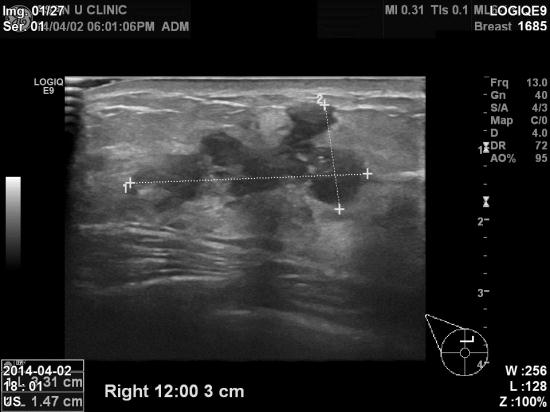

우측유방에 만져지는 멍우리를 주소로 내원하신

44

여자분이십니다

본원초음파상 우측유방 12시방향 젖꼭지에서

3cm

어진 부위에 3.31 cm

종괴가발견되었고

우측겨드랑이에도 림프절 비대소견있어 조직검사와

세포검사를 시행하였습니다